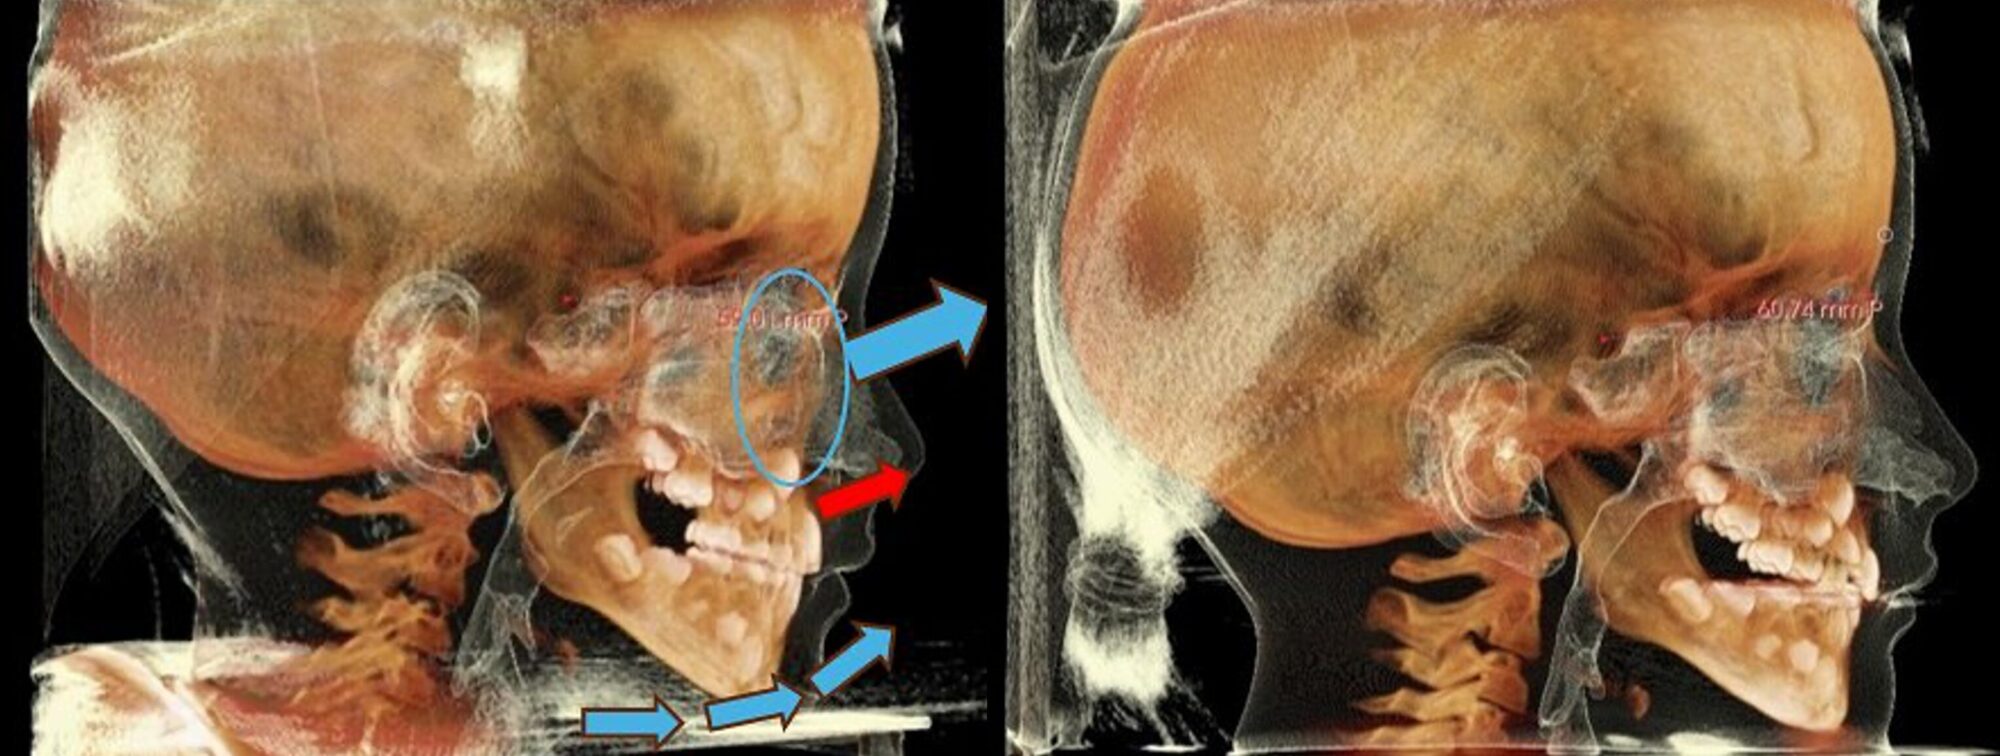

RAMPAで前上方へ

下方へ向かうことになった成長の結果が、顎骨の歪みに繋がります。

これに対して、RAMPAのシステムから、その成長方向を前上方へと変化させ、歪みの解消を目指します。

この変化によって、狭くなった鼻腔や副鼻腔、気道、顎に対して「拡がる」という効果を見込むことができます。本来は「前上方」へ成長するはずだったのです。

「前方」でも「前下方」でもありません。

イラスト左の青矢印は、RAMPAによる改善効果とお考えいただいても大きな支障はありません。ただ、中顔面(上顎)が上がらなければ、下顎は上がりません。

RAMPAの装置を、お約束通り装着でき、順調な経過を辿ると、中顔面(青丸)全体から上前方へ成長方向が変化します。装着時間が足りないと赤矢印のような口元だけの変化になることがあります。

※RAMPAによる骨格の変化のイメージとしてCG動画はご覧ください。受け口に対して、下の顎を引っ込めるという動きはしていません。不正咬合の原因のほとんどは上下の顎の劣成長であって、過成長ではありません。舌骨の位置の変化にも注目してみてください。